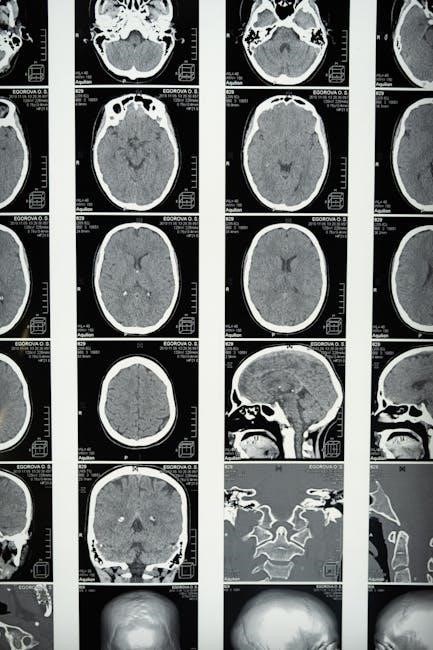

This article will comprehensively examine the neurological changes associated with pornography consumption, building upon the foundation laid by research highlighted on YourBrainOnPorn.com. We will investigate alterations in brain structure, specifically focusing on gray matter volume reductions observed in MRI studies, particularly in regions crucial for complex thinking.

Furthermore, we will explore disruptions in functional connectivity, analyzing how pornography use impacts resting-state brain activity and alters neural pathways related to impulse control. A key focus will be the dopamine release within the reward system, and its role in reinforcing compulsive behaviors. We will also draw parallels between pornography addiction and substance addiction, examining shared neurological mechanisms. The aim is to provide a detailed overview of the brain’s response, utilizing findings from voxel-based morphometry (VBM), fMRI, and fNIRS studies.

MRI studies demonstrate that frequent pornography consumption correlates with reduced gray matter volume, impacting areas vital for higher-level cognitive functions and emotional regulation.

Research consistently indicates a correlation between extensive pornography consumption and a discernible reduction in gray matter volume within specific brain regions. This gray matter, crucial for complex cognitive processes like decision-making, impulse control, and emotional processing, appears to diminish with prolonged exposure. Studies utilizing voxel-based morphometry (VBM) have pinpointed areas such as the prefrontal cortex and the insula as particularly vulnerable to these structural changes.

The implications of this reduction are significant, potentially leading to impaired executive functions and a decreased ability to regulate behaviors. Essentially, the brain tissue responsible for nuanced thought and self-control may physically shrink, contributing to compulsive patterns and difficulties in maintaining healthy relationships. This structural alteration isn’t necessarily permanent, but prolonged exposure exacerbates the effect, highlighting the importance of understanding these neurological consequences.

Functional connectivity, measured during rest, reveals how different brain regions communicate. Research indicates pornography consumption significantly alters these baseline connections. Specifically, studies employing 3-Tesla MRI have demonstrated disruptions in the brain’s default mode network and other critical circuits.

Pornography consumption demonstrably impacts neural pathways crucial for impulse control, particularly those involving the prefrontal cortex. MRI studies reveal heavy users exhibit reduced grey matter in this region, directly correlating with diminished executive functions like decision-making and self-regulation.

Consistent exposure to highly stimulating pornographic content can lead to strengthening of specific neural pathways associated with reward and arousal, while simultaneously weakening others. MRI studies, as highlighted by the MMHC, demonstrate a correlation between heavy pornography use and reduced gray matter volume – the brain tissue crucial for complex cognitive functions like decision-making and impulse control.

Voxel-Based Morphometry (VBM) is a neuroimaging technique employed to investigate regional differences in brain structure. Research utilizing VBM has consistently demonstrated a correlation between pornography consumption and alterations in gray matter volume. Specifically, studies indicate that individuals who frequently consume pornography often exhibit reduced gray matter in several brain regions.

Notably, these reductions are frequently observed in the prefrontal cortex, an area crucial for decision-making, impulse control, and executive functions. Furthermore, diminished gray matter has been reported in regions associated with reward processing and motivation. These structural changes, identified through VBM, suggest that prolonged pornography use may impact cognitive abilities and contribute to compulsive behaviors.

The implications of these findings are significant, as gray matter volume is directly linked to neuronal density and synaptic connections, impacting overall brain function and potentially contributing to addictive patterns.

Functional Magnetic Resonance Imaging (fMRI) allows researchers to observe brain activity by detecting changes associated with blood flow. fMRI studies examining pornography consumption reveal heightened activation in the nucleus accumbens, a key component of the brain’s reward system, mirroring responses to addictive substances. This intense activation contributes to the reinforcing effects of pornography, driving compulsive use.

Furthermore, fMRI has identified altered neural pathways and disrupted functional connectivity, particularly in regions involved in impulse control and decision-making. These disruptions suggest a diminished capacity to regulate urges and resist pornography-seeking behaviors. Research also demonstrates altered resting-state functional connectivity, indicating changes in brain network organization even when not actively viewing pornography.